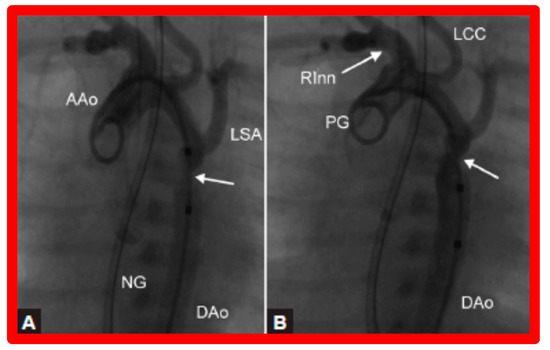

- Rao, P.S.; Wilson, A.D.; Brazy, J. Transumbilical balloon coarctation angioplasty in a neonate with critical aortic coarctation. Am. Heart J. 1992, 124, 1622–1624. [Google Scholar] [CrossRef]